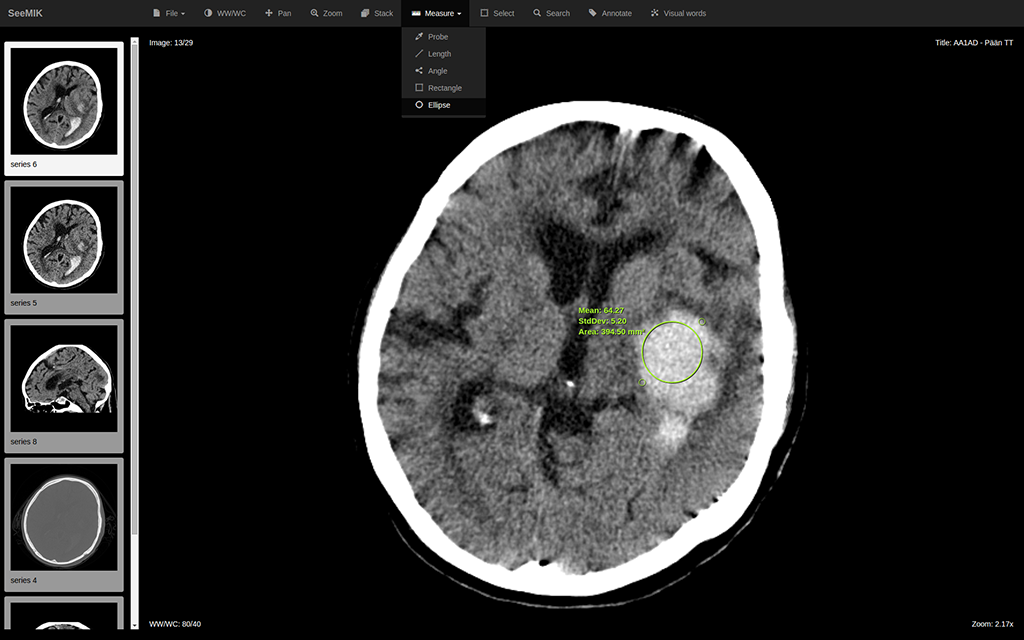

If radiologist is not sure which diagnosis better relates to existing findings, then he/she points out the feature of interest in the medical image and defines keywords.

• Data processing

SeeMIK finds keys for images with similar-appearing features and study reports related to keywords in index. It obtains by found keys real data from PACS and RIS and then shows it to radiologist.